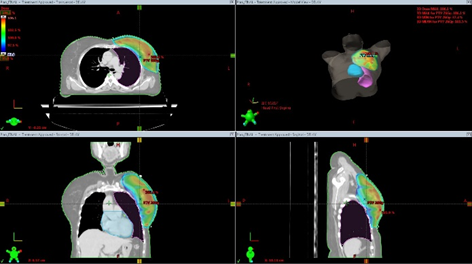

A forward planning 3D-CRT technique  was used for radiotherapy planning.The treatment planning software was Eclipse version 13.6 with AAA algorithm. A primary pair of tangential beams with a field in field technique using  a few subfields of variable beam weightage were utilised to get a homogenous dose distribution and conformity. Photons beams of 6MV energy were used in all our  cases. The isocentre was placed at the centre of whole breast PTV or on the centre of the tumour bed. Weightage of beams were modified and adjusted so that adequate dose  coverage was ensured to the target volume without creating hotspots outside.MLC shaping helps in shielding of heart and lung(   Picture 3).

For the boost planning multiple mini tangential and oblique subfields were used.

Picture 3-Radiotherapy beam arrangements